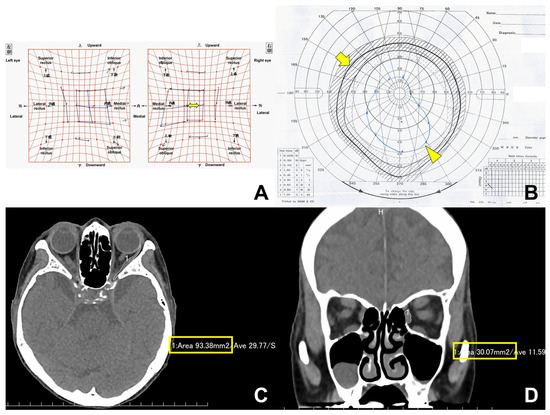

Background and Objectives: The purpose of this study was to evaluate the outcome of lateral rectus (LR) muscle resection for new-onset or worsening esotropia after medial orbital wall decompression in patients with thyroid eye disease. Materials and Methods: This retrospective observational study included [...] Read more.

Background and Objectives: The purpose of this study was to evaluate the outcome of lateral rectus (LR) muscle resection for new-onset or worsening esotropia after medial orbital wall decompression in patients with thyroid eye disease. Materials and Methods: This retrospective observational study included 20 patients. Preoperative and postoperative measurements of ocular deviation angles and fields of binocular single vision (BSV) were performed one day before and three months after surgery. Surgical success was defined as postoperative horizontal ocular deviation ≤ 5° and BSV including the primary position. Factors influencing a reduction in the esodeviation angle were analyzed using univariate and multivariate linear regression analyses. Results: Eighteen patients (90.0%) were deemed as successful surgical cases. The esodeviation angle decreased from 19.4 ± 11.2° to 1.0 ± 2.6°. In multivariate analysis, a reduction in the esodeviation angle was correlated with the presence of dysthyroid optic neuropathy (p = 0.027), amounts of LR muscle resection in mild eyes (p = 0.014), and amounts of additional medial rectus muscle recession in severe eyes (p < 0.001). Conclusions: LR muscle resection showed a high success rate in correcting new-onset or worsening esotropia which developed after medial orbital wall decompression. Several factors influencing a reduction in the esodeviation angle were found. Full article